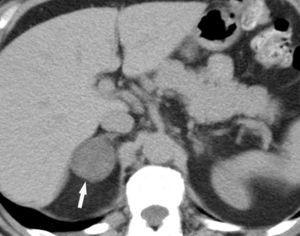

Metástasis hepáticas y suprarrenales

La aparición de nódulos suprarrenales se da en más del 10% de los pacientes con cáncer de pulmón. Dada la elevada frecuencia de adenomas benignos, es crucial la distinción entre éstos y la afectación metastásica. Ésta se puede llevar a cabo con una combinación de estrategias de imagen que incluyen TC, RM y/o PET. Por TC los adenomas suprarrenales típicamente tienen valores de atenuación bajos por la presencia de cúmulos lipídicos. Una lesión suprarrenal con valores de atenuación menores de 10 unidades Hounsfield (UH) en el estudio sin contraste, tiene una probabilidad del 98% de que se trate de una lesión benigna. Dado que ambas lesiones, adenomas y metástasis captan contraste, la valoración rutinaria de la captación no es útil en la diferenciación entre benignidad y malignidad. Si se detecta durante la realización de la TC, realizar cortes tardíos a los 15 minutos de la administración de contraste es importante, ya que si existe un lavado del contraste de más del 50% el diagnóstico de adenoma tiene una sensibilidad del 98% y una especificidad que oscila entre el 92 y el 100%20. La RM con secuencias de desplazamiento químico en la valoración de nódulos suprarrenales tiene una especificidad del 100% para el diagnóstico de adenoma (fig. 14). Sin embargo, la sensibilidad depende de la densidad de la lesión en el estudio con TC, ya que cuanto mayor es la densidad en la TC menos señal perderá en la RM, con lo que resulta más difícil etiquetarlo como adenoma21. La PET presenta una sensibilidad alta en la detección de metástasis suprarrenales, ya que cuando una lesión suprarrenal no muestra signos concluyentes en la TC de benignidad, la ausencia de actividad con la PET hace muy probable dicho diagnóstico. En los casos en que persistan dudas diagnósticas se debe recurrir a la biopsia de la lesión adrenal, especialmente si de este diagnóstico depende el manejo del paciente.